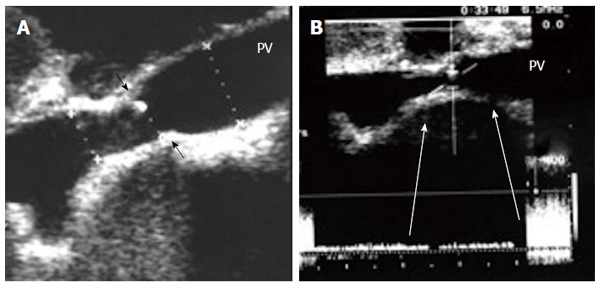

Figure 19.

Portal vein pseudo-stenosis in a clinically silent patient. A: Post- operative color Doppler image, 2 mo post living donor liver transplantation demonstrating anastomotic stenosis 50%-60%, with elevation of the anastomotic velocity (4-fold) compared to the pre-anastomotic velocity; B: Percutaneous trans-hepatic digital subtraction portography image, showing anastomotic stricture (arrows) however, the pressure gradient across the anastomosis was 3 mmHg and angioplasty and stent placement were not performed. PV: Portal vein; HA: Hepatic artery.

It is necessary to differentiate between PVS and PV size mismatch by DU. PV calibre differences appear on b-mode US as tapering of the anastomosis without encroachment of the suture line on the lumen. By pulsed Doppler, elevations of the anastomotic velocities (usually < 3-fold) compared to the pre-anastomotic velocities are apparent (Figure 11). In PVS, encroachment of the suture line on the lumen can cause focal color aliasing with > 3-fold elevation of the anastomotic velocities by Color Doppler flow (Figures 20, 21 and 22). Haemodynamically significant stenosis may produce post-stenotic aneurysmal dilation as well[78] (Figure 23). A PV stenotic ratio has been proposed to define the degree of stenosis using the formula: PV stenotic ratio (%) = pre-stenotic calibre-anastomotic calibre/pre-stenotic calibre. Anastomotic calibre < 5 mm and stenotic ratio > 50% have been defined as the critical points for PVS cases that require interventional management for good long-term graft survival[87]. In equivocal cases, MDCT can confirm the morphological degree of the stricture and other signs of portal hypertension but will not provide quantitative information about the degree of stricture. A PVP gradient across the anastomosis can be performed in the recipient surgery or during the PO interventional angioplasty procedures, pressure gradients > 3-5 mmHg are considered significant and necessitate intervention[81,88] (Figure 21).